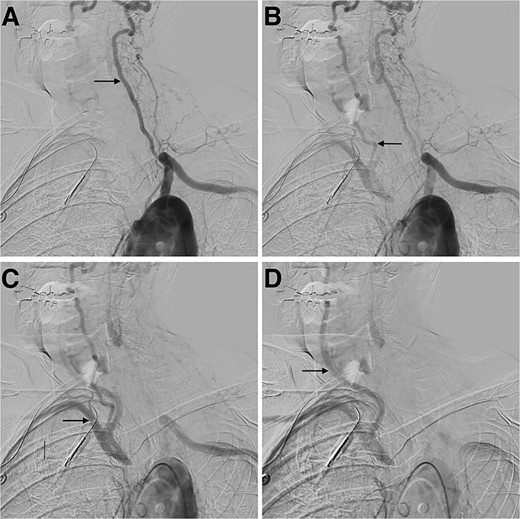

The patient was assessed for endovascular revascularization of the innominate artery. Right radial access and right femoral access were obtained. A pigtail catheter was advanced by the femoral access to obtain an aortic arch image and confirm the location of the catheter at the brachycephalic artery (Fig. 3A). Moreover, the radial access advanced a stiff glide wire, and a large bore catheter was advanced over it. Furthermore, a Gore Viabahn VBX Balloon Expandable Stent (W.L. Gore & Associates, Flagstaff, AZ, USA) was introduced and, under roadmap guidance, crossed the site of obstruction, completing the revascularization (Fig. 3B). The patient was discharged and referred for rehabilitation a few days later with a disappearance of the symptoms.

Digital subtraction angiogram demonstrating: (A) brachiocephalic artery occluded before the stent placement. (B) Brachiocephalic artery opened after the introduction of the Gore Viabahn VBX Balloon Expandable Stent (W.L. Gore & Associates, Flagstaff, AZ, USA).